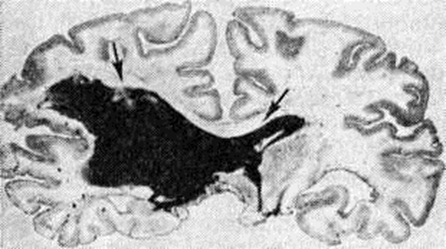

Геморрагический инсульт, как правило, возникает при заболеваниях, протекающих с повышенным артериальное давление. Это обусловлено тем, что сосудистые кризы (смотри полный свод знаний), характерные для гипертонической болезни (смотри полный свод знаний) и артериальной гипертензии (смотри полный свод знаний Гипертензия артериальная), приводят к морфологический изменениям стенок внутримозговых сосудов с нарушением их проницаемости — плазматическому пропитыванию (рисунок 1), некрозам (рисунок 2), образованию микроаневризм (рисунок 3) и их разрывам. Разрыв врождённых артериальных и артериовенозных аневризм может протекать на фоне нормального давления. Преимущественная локализация и характер геморрагий определяются особенностями ангиоархитектоники различных отделов мозга. При гипертонической болезни наиболее тяжёлым изменениям подвергаются сосуды подкорковых узлов и зрительного бугра. Это объясняется отхождением глубоких ветвей под прямым углом от средней мозговой артерии, являющейся продолжением внутренней сонной артерии, и незначительным числом анастомозов сосудов в этой области. В связи с этим на вскрытии кровоизлияния наиболее часто (40%) обнаруживаются в подкорковых узлах с распространением в прилежащее белое вещество (так называемый латеральные кровоизлияния, то есть расположенные латерально от внутренней капсулы, рисунок 4). Второе место по частоте (16%) занимают обширные кровоизлияния, разрушающие подкорковые узлы, внутреннюю капсулу, зрительный бугор (так называемый смешанные кровоизлияния — рисунок 5). Кровоизлияния в зрительный бугор (так называемый медиальные — рисунок 6) составляют 10%, в мозжечок — 6—10%, в мост мозга — 5% от общего числа внутримозговых геморрагий. Кровоизлияния только в белое вещество полушарий мозга встречаются крайне редко. Подразделение полушарных кровоизлияний на латеральные, медиальные и смешанные имеет особое значение в связи с хирургическим лечением геморрагического Инсульт.

Рис. 5. | ||